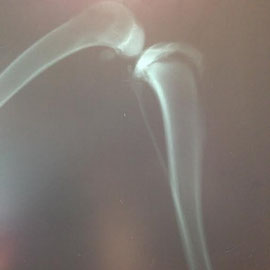

Le lendemain, c’est Alegra qui est portée au refuge. Elle a été trouvée errante dans la rue, boitant de la patte arrière gauche. Première supposition : une fracture des ligaments ?

Après examen, il semblerait que le problème se trouve au niveau du genou car il y a douleur à la palpation. Les radios montrent une fracture du plateau tibial, avec un léger déplacement de la tête. Une intervention chirurgicale est recommandée pour poser des broches.

- ALEGRA a une fracture du plateau tibial, ce qui arrive en général sur chez de jeunes chiens (6/8 mois). En général, la prise en charge doit avoir lieu dans les jours qui suivent, faute de cela, on risque fort de ne rien pouvoir faire… Depuis combien de temps la belle souffre-t-elle ainsi ? Il existe deux solutions. Une qui consiste à ne rien toucher dans l’espoir que sa patte se consolide, l’autre qui consiste en une opération de consolidation (mise en place d’une sorte d’attèle pour ne pas forcer sur la patte). Le coût prévu pour son opération est de 450€.